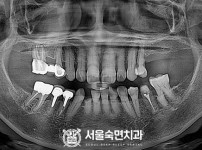

임플란트-전후사진2